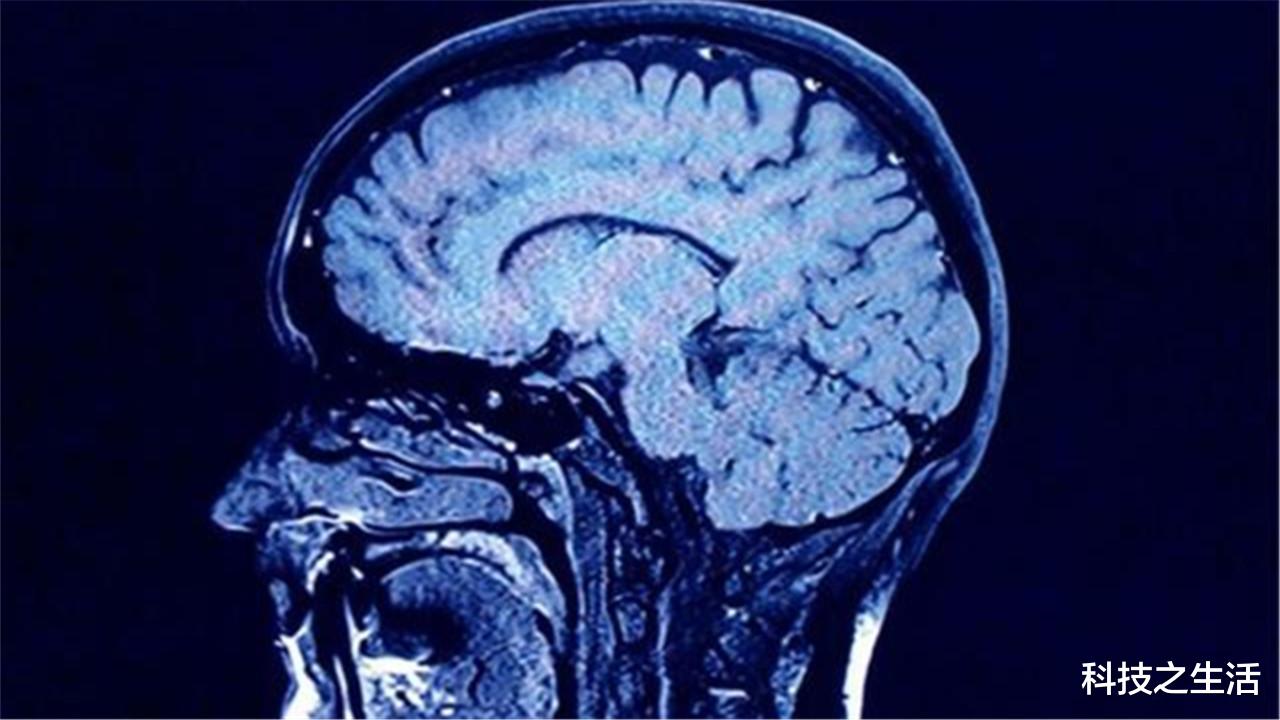

随着各个国家对火星探测历程的加快 , 第1批登上火星的人将会接受重大的考验 。 科学家这么多年来 , 一直在实时跟踪宇航员的身体变化 。 当进入宇宙后 , 他们的大脑会肿大变形 , 这对于他们的身体会造成严重的创伤 。 一位科学家就对宇航员进行了这样的测试 , 科学家在他进入国际空间站之前扫描了一次大脑 , 在他返回地球后又扫描了一次 。 结果发现当他进入太空后 , 大脑的体积开始变大 , 血液凝聚在了视觉神经中 , 大脑开始变形 。

如果长时间在真空环境中 , 大脑和脑积液将会持续膨胀 , 虽然它们也可以对大脑起到保护作用 , 但长久来看 , 对身体健康是有不利影响的 。 科学家认为大脑所产生的变化 , 就像长期卧床的患者一样 。 那么是什么原因造成了脑积液体积增大的原因呢?科学家认为这或许与大脑聚集的蛋白质有关 。

当宇航员进入真空环境后 , 他们的脑垂体就开始缩小 。 正常的脑纹路是比较平整的 , 进入太空后就变成突起了 。 这其实都是颅内压升高导致的 。 虽然直到如今 , 在国际空间站工作额人员并未在体检报告中写明这一项 , 但科学家认为 , 宇航员进入太空后所面临的问题远不止于此 , DNA破坏、免疫系统紊乱、强烈的辐射 , 这些都是危害人类健康的“杀手” 。